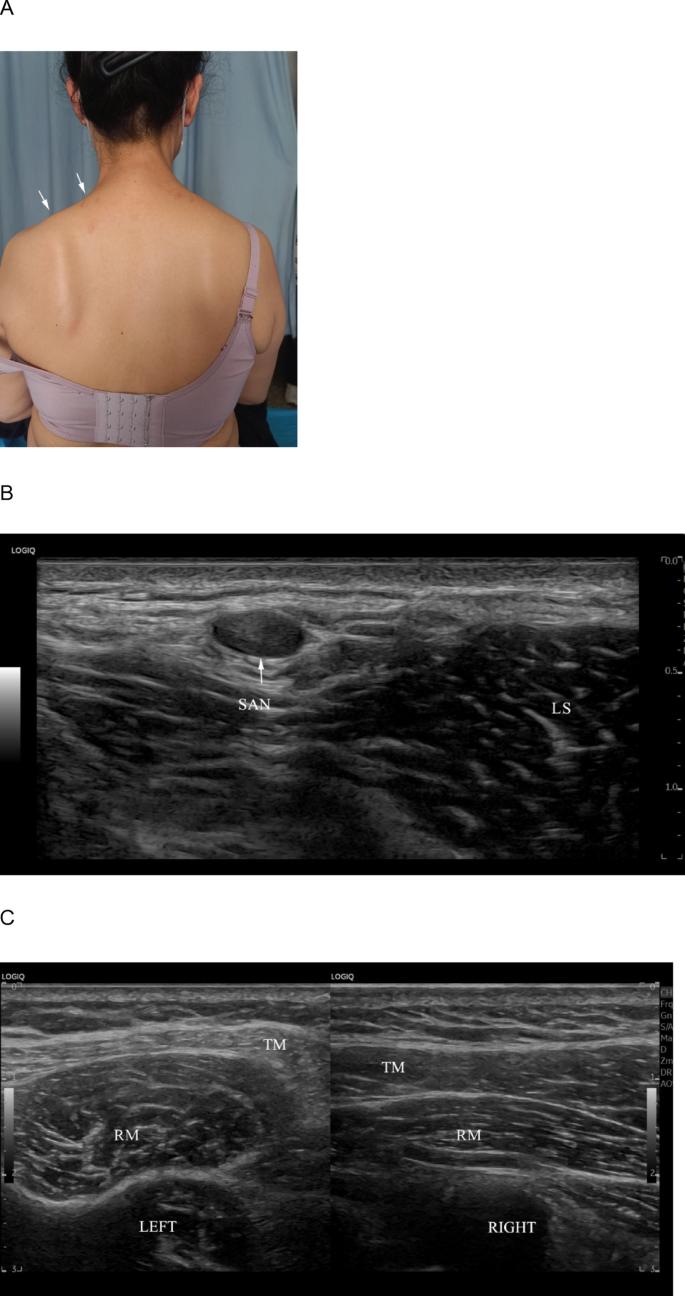

From July 2022 to March 2024, 12 patients were diagnosed with SAN injury through HRUS, confirmed by surgery or MRI. All patients had a history of neck surgery or trauma, including 7 cases of cervical lymph node biopsy, 3 cases of vascular anomaly surgery, and 2 cases of knife injury. Among these, 5 injuries were in segment S3, and 7 were in segment S2. Pathologic SANs showed characteristic changes: diffusely increased intraneural echogenicity consistent with neural fibrosis (the so-called “white nerve”), loss of normal fascicular definition, and caliber alterations. In cases with discontinuity, HRUS demonstrated complete nerve rupture with retracted proximal/distal stumps and bulbous traumatic neuroma at the ends in some patients, often accompanied by trapezius muscle atrophy and increased echogenicity of the affected muscle (Figs. 5, 6, Supplementary Video S1 and Supplementary Video S2). All 12 patients underwent surgical treatment.

A 42-year-old female presented with left shoulder elevation weakness six months after a lymph node biopsy. A A clinical photograph shows left shoulder drooping and winged scapula. B High-resolution ultrasound (short-axis) at S2 shows rupture of the spinal accessory nerve (SAN) with traumatic neuroma (TN) on the affected side; the nerve lies superficial to the levator scapulae (LS). C Ultrasound of the trapezius (TM) on the affected side demonstrates denervation atrophy (thinning and increased echogenicity), with the underlying Rhomboids (RM) labeled for orientation.

Supplementary Video 1. A 42-year-old female presented with left shoulder elevation weakness six months after a lymph node biopsy. Ultrasonography reveals a rupture of the spinal accessory nerve (SAN) at S2 and traumatic neuroma (TN) formation.